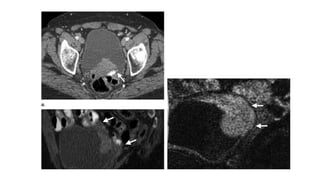

• #28 Urothelial carcinoma (stage T2b) in a 62-year-old woman. (a, b) Axial (a) and sagittal (b) contrast-enhanced CT scans show an irregular 4.6-cm hyperattenuating mass at the posterosuperior bladder wall (arrows). There is a suggestion of small bowel involvement. (c) Sagittal diffusion-weighted image shows tumor extension into the bladder wall without perivesical involvement (arrows). Results of TURBT confirmed stage T2b disease.

• #30 Metastatic urothelial carcinoma man who undergone TURBT 1 year earlier. (a) Axial fat-suppressed spoiled GRE image shows a left external iliac lymph node (arrow) with a maximum diameter of 1.5 cm. (b) axial diffusion-weighted image, the left external iliac lymph node (arrow) demonstrates high signal intensity and a low ADC value of 0.75 ×10-3 mm2/sec, findings that are suggestive of malignancy. Bilateral lymphadenectomy helped confirm metastatic transitional cell carcinoma in the left external iliac lymph node chain.